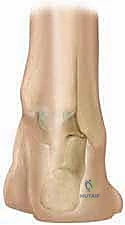

4. تحرير الكبسولات المفصلية (Capsulotomy):

لإعادة العظام إلى وضعها الطبيعي، يجب قطع أو تحرير الأربطة والكبسولات المحيطة بالمفاصل المتيبسة، وتحديداً:

* الكبسولة الخلفية لمفصل الكاحل (Ankle Joint).

* الكبسولة الخلفية والإنسية للمفصل تحت القنزعي (Subtalar Joint).

* مفصل الكعب النردي (Calcaneocuboid Joint) في حالات التحرير الوحشي.

5. التثبيت بأسلاك كيرشنر (K-wires Fixation):

بعد استعادة الوضع التشريحي المثالي للقدم، يقوم الدكتور هطيف بتثبيت العظام في وضعها الجديد باستخدام أسلاك معدنية دقيقة (أسلاك كيرشنر). تمر هذه الأسلاك عبر المفاصل لضمان عدم تحركها أثناء فترة الالتئام.